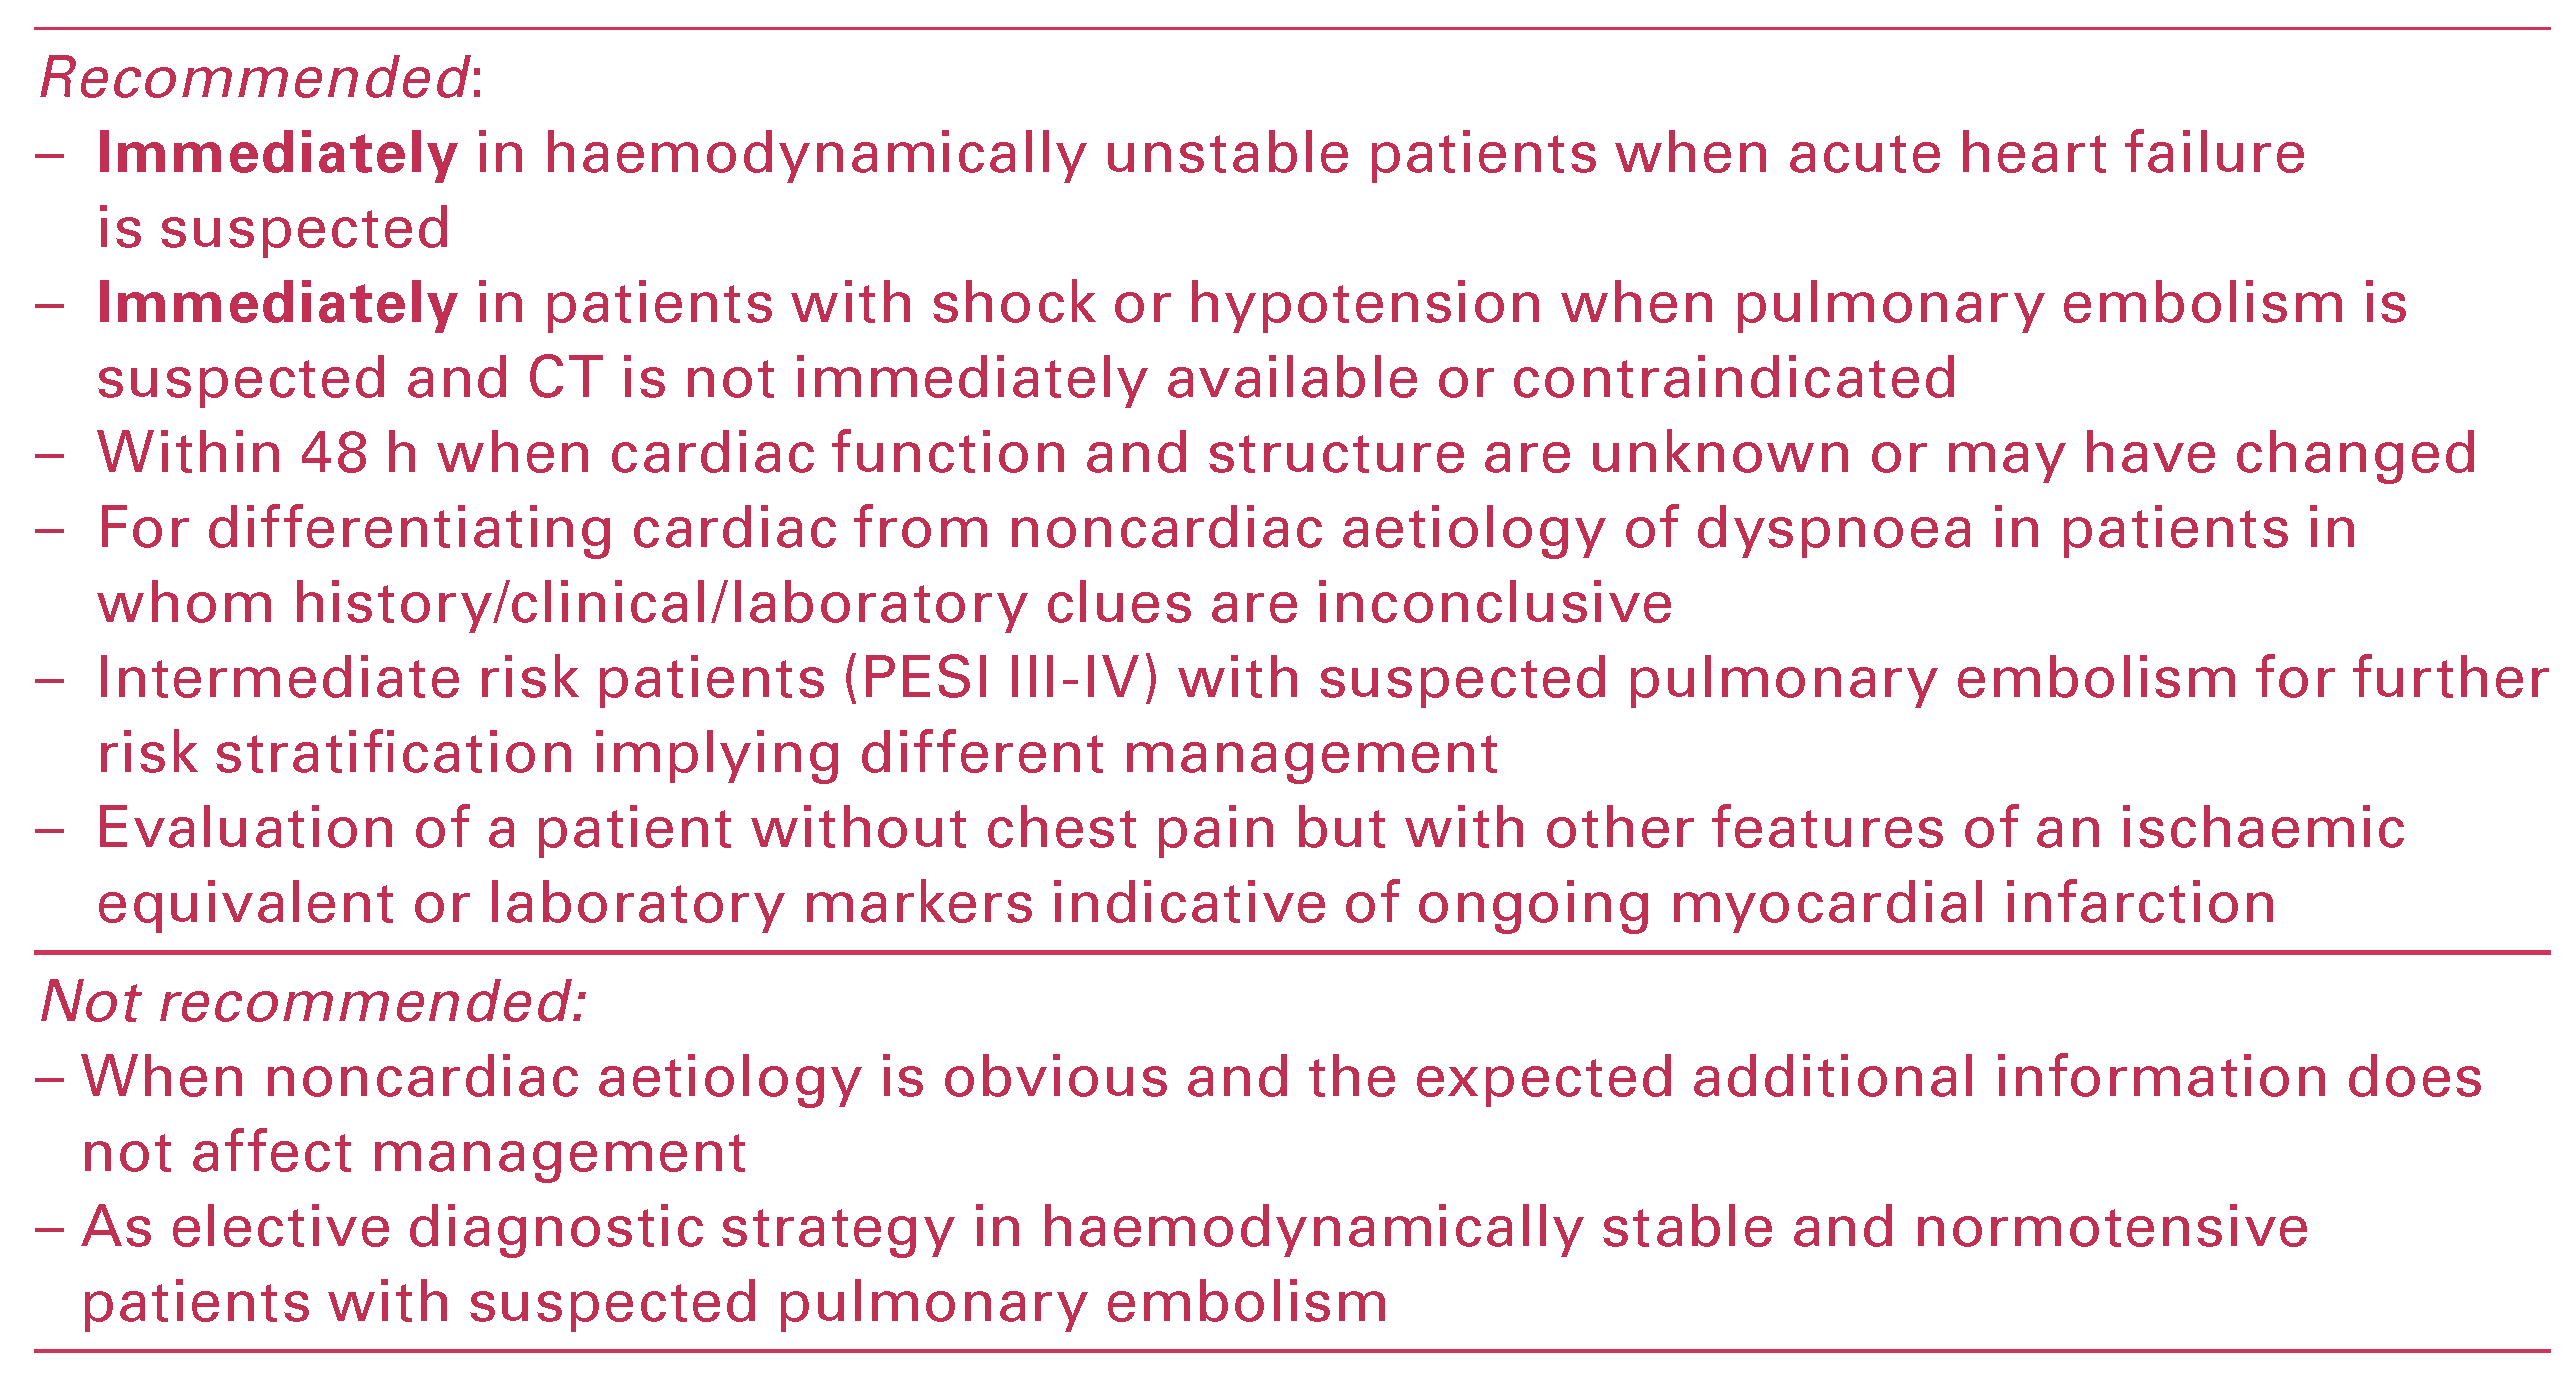

Appropriate Use Criteria

In an effort to define a reasonable application of cardiac ultrasound, the American College of Cardiology Foundation (ACCF) and the American Society of Echocardiography (ASE) reviewed various clinical scenarios and assessed various indications for echocardiography as appropriate, uncertain or inappropriate, according to the available evidence-based information and expert clinical experience. Appropriate cardiac ultrasound is expected to improve clinical outcome in a cost-effective manner; inappropriate use may likely be harmful for patients and/or cause extra cost (

Table 2) [

13]. Although appropriate use criteria provide reasonable indications for application of echocardiography, the essential role of clinical judgment and experience in the management of individual patients should be stressed. Furthermore, it is important to emphasise that most of the appropriate indications for echocardiography in patients with acute dyspnoea require a comprehensive echocardiographic examination and cannot be accomplished adequately by a focused cardiac ultrasound [

14].